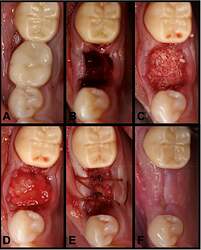

Figure 2.

(A) Preoperative clinical photograph. (B) After extraction of tooth #30, the socket was degranulated with a spoon excavator leaving a socket with a buccal dehiscence present. (C) The extraction socket was grafted with “sticky bone.” (D) The e‐PRF membrane was then placed over the grafted socket and (E) sutured with 3‐0 chromic gut in mattress fashion. (F) The patient was brought back for a 2‐week postoperative evaluation. Note the excellent healing and near complete wound closure.